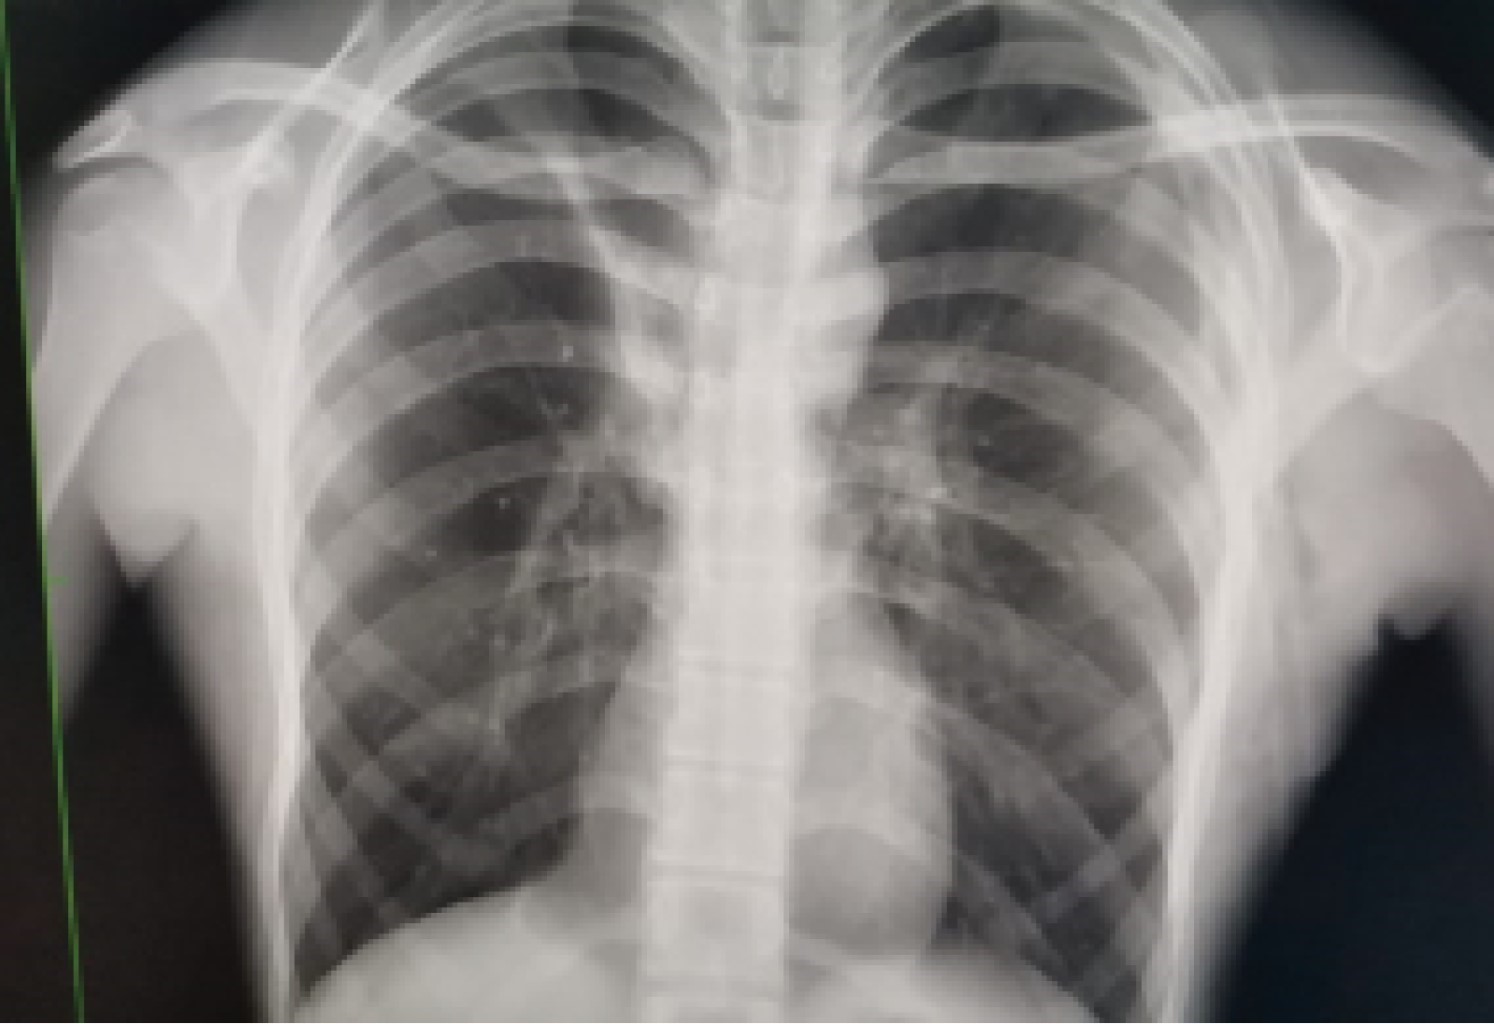

Three weeks later, he came to the emergency department referring a two-day evolution of pain in the left hemithorax, of sudden onset, transfixing, as well as dyspnea at rest; the physical examination revealed hypoventilation of the left hemithorax and hyper resonance to percussion. The X-ray showed recurrent pneumothorax (Figure 1) and an endo pleural probe was placed. Adequate pulmonary expansion was seen on X-ray (Figure 2). Seven days later the patient underwent a seal pleural probe test, presenting dyspnea and chest pain. A control X-ray showed recurrent left pneumothorax (Figure 3), so a CT scan was requested, showing persistent pneumothorax, and left apical bulla, so a surgical protocol for thoracoscopy was initiated.

Figure 2